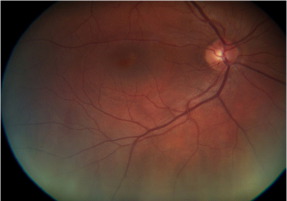

Figure 1c OCT demonstrates a focal detachment of retinal pigment epithelium of the macula of 558μm.

Medical treatment consisting of non-steroidal, anti-inflammatory eye drops and acetazolamid tablets was started. Five months later- the patient missed her 2 months examination- the patient gained full visual acuity (20/20). The OCT showed a complete resolution of the neurosensory retinal detachment with a foveal thickness of 276μm (Figure 2). A second FA was not performed with respect to the patient, who was at that time still breastfeeding.

Figure 2 RA: OCT 5 months after delivery and treatment with non-steroidal anti-inflammatory eye drops and carbonic anhydrase inhibitor tablets. Visual acuity returned to 20/20 with a retinal thickness of 276μm.